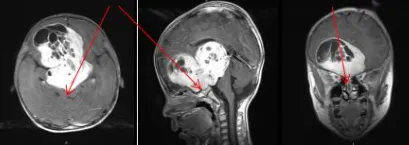

5岁男性患儿患有巨大视路胶质瘤。首次术后鞍区及第三脑室肿瘤残余较大,双侧视神经受肿瘤侵犯,下丘脑严重受压,左侧脑室积水明显,临床症状未获明显改善。由于视神经被肿瘤浸润包裹,完全剥离难度极大,面临失明风险。多家医疗机构认为患儿无法再次手术。

为保障患儿安全及提高切除率,巴教授与Concezio Di Rocco教授决定实施联合手术。通过额骨颅骨开颅术和大脑半球间穹窿入路切除肿瘤至Monro孔(室间孔),并沿脑室壁向中脑行进。右侧视神经被肿瘤浸润包裹,但左侧视神经被小心地从肿瘤肿块中剥离,垂体腺和垂体柄得到妥善保护,无术中并发症。第三脑室占位完全切除,鞍上占位基本全切,视神经及周围血管保持完整。